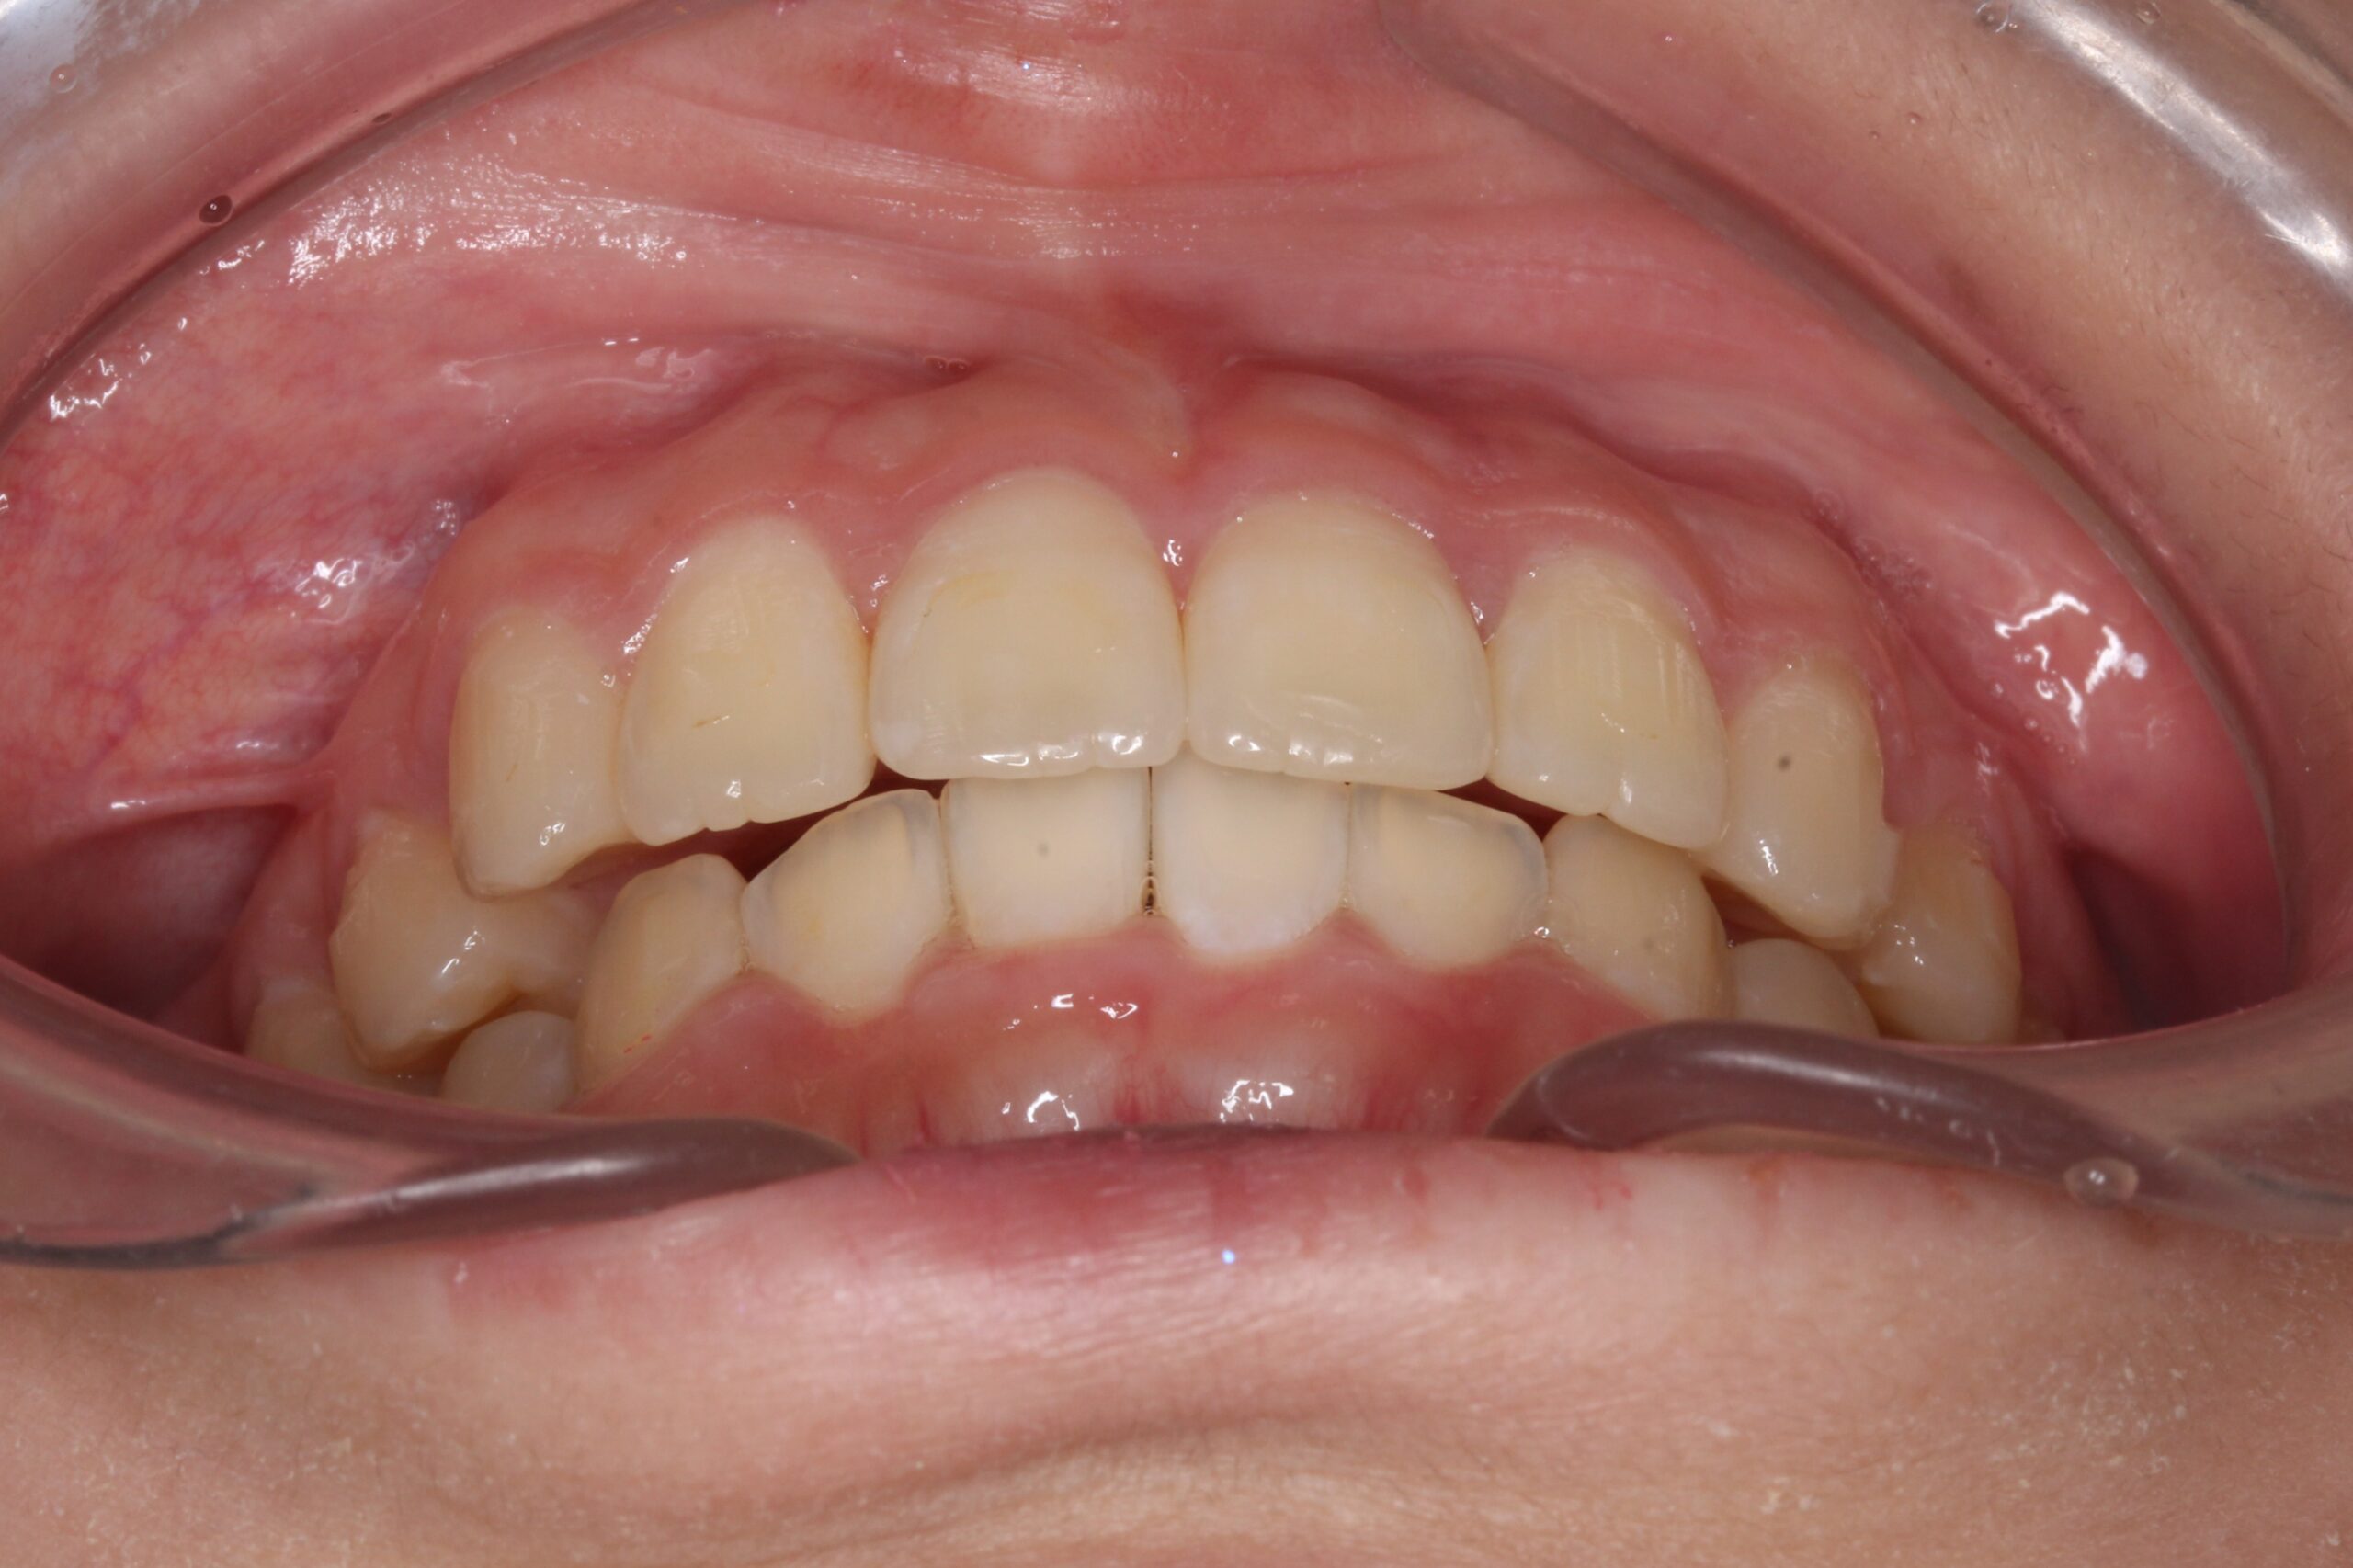

矯正術前:正面

矯正術後:正面